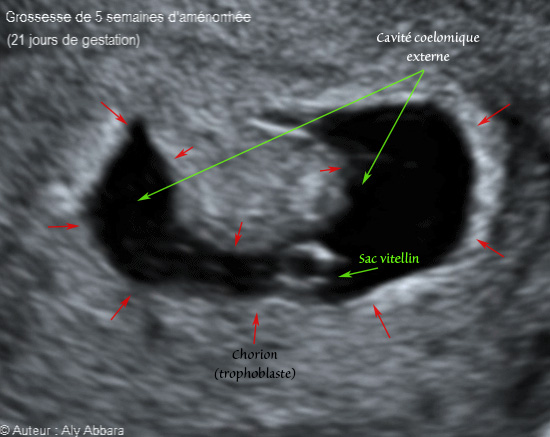

• • Images échographiques montrant un sac gestationnel évoluant dans la cavité utérine correspondant à 20 à 21 jours de gestation (soit la fin de la 5e semaine d'aménorrhée).

• Ces images montrent un sac gestationnel composé essentiellement :

° d'une cavité cœlomique externe limitée par le chorion qui s'insère sur l'endomètre ; cette cavité cœlomique externe contient :

* Seulement le sac vitellin sans image embryonnaire.